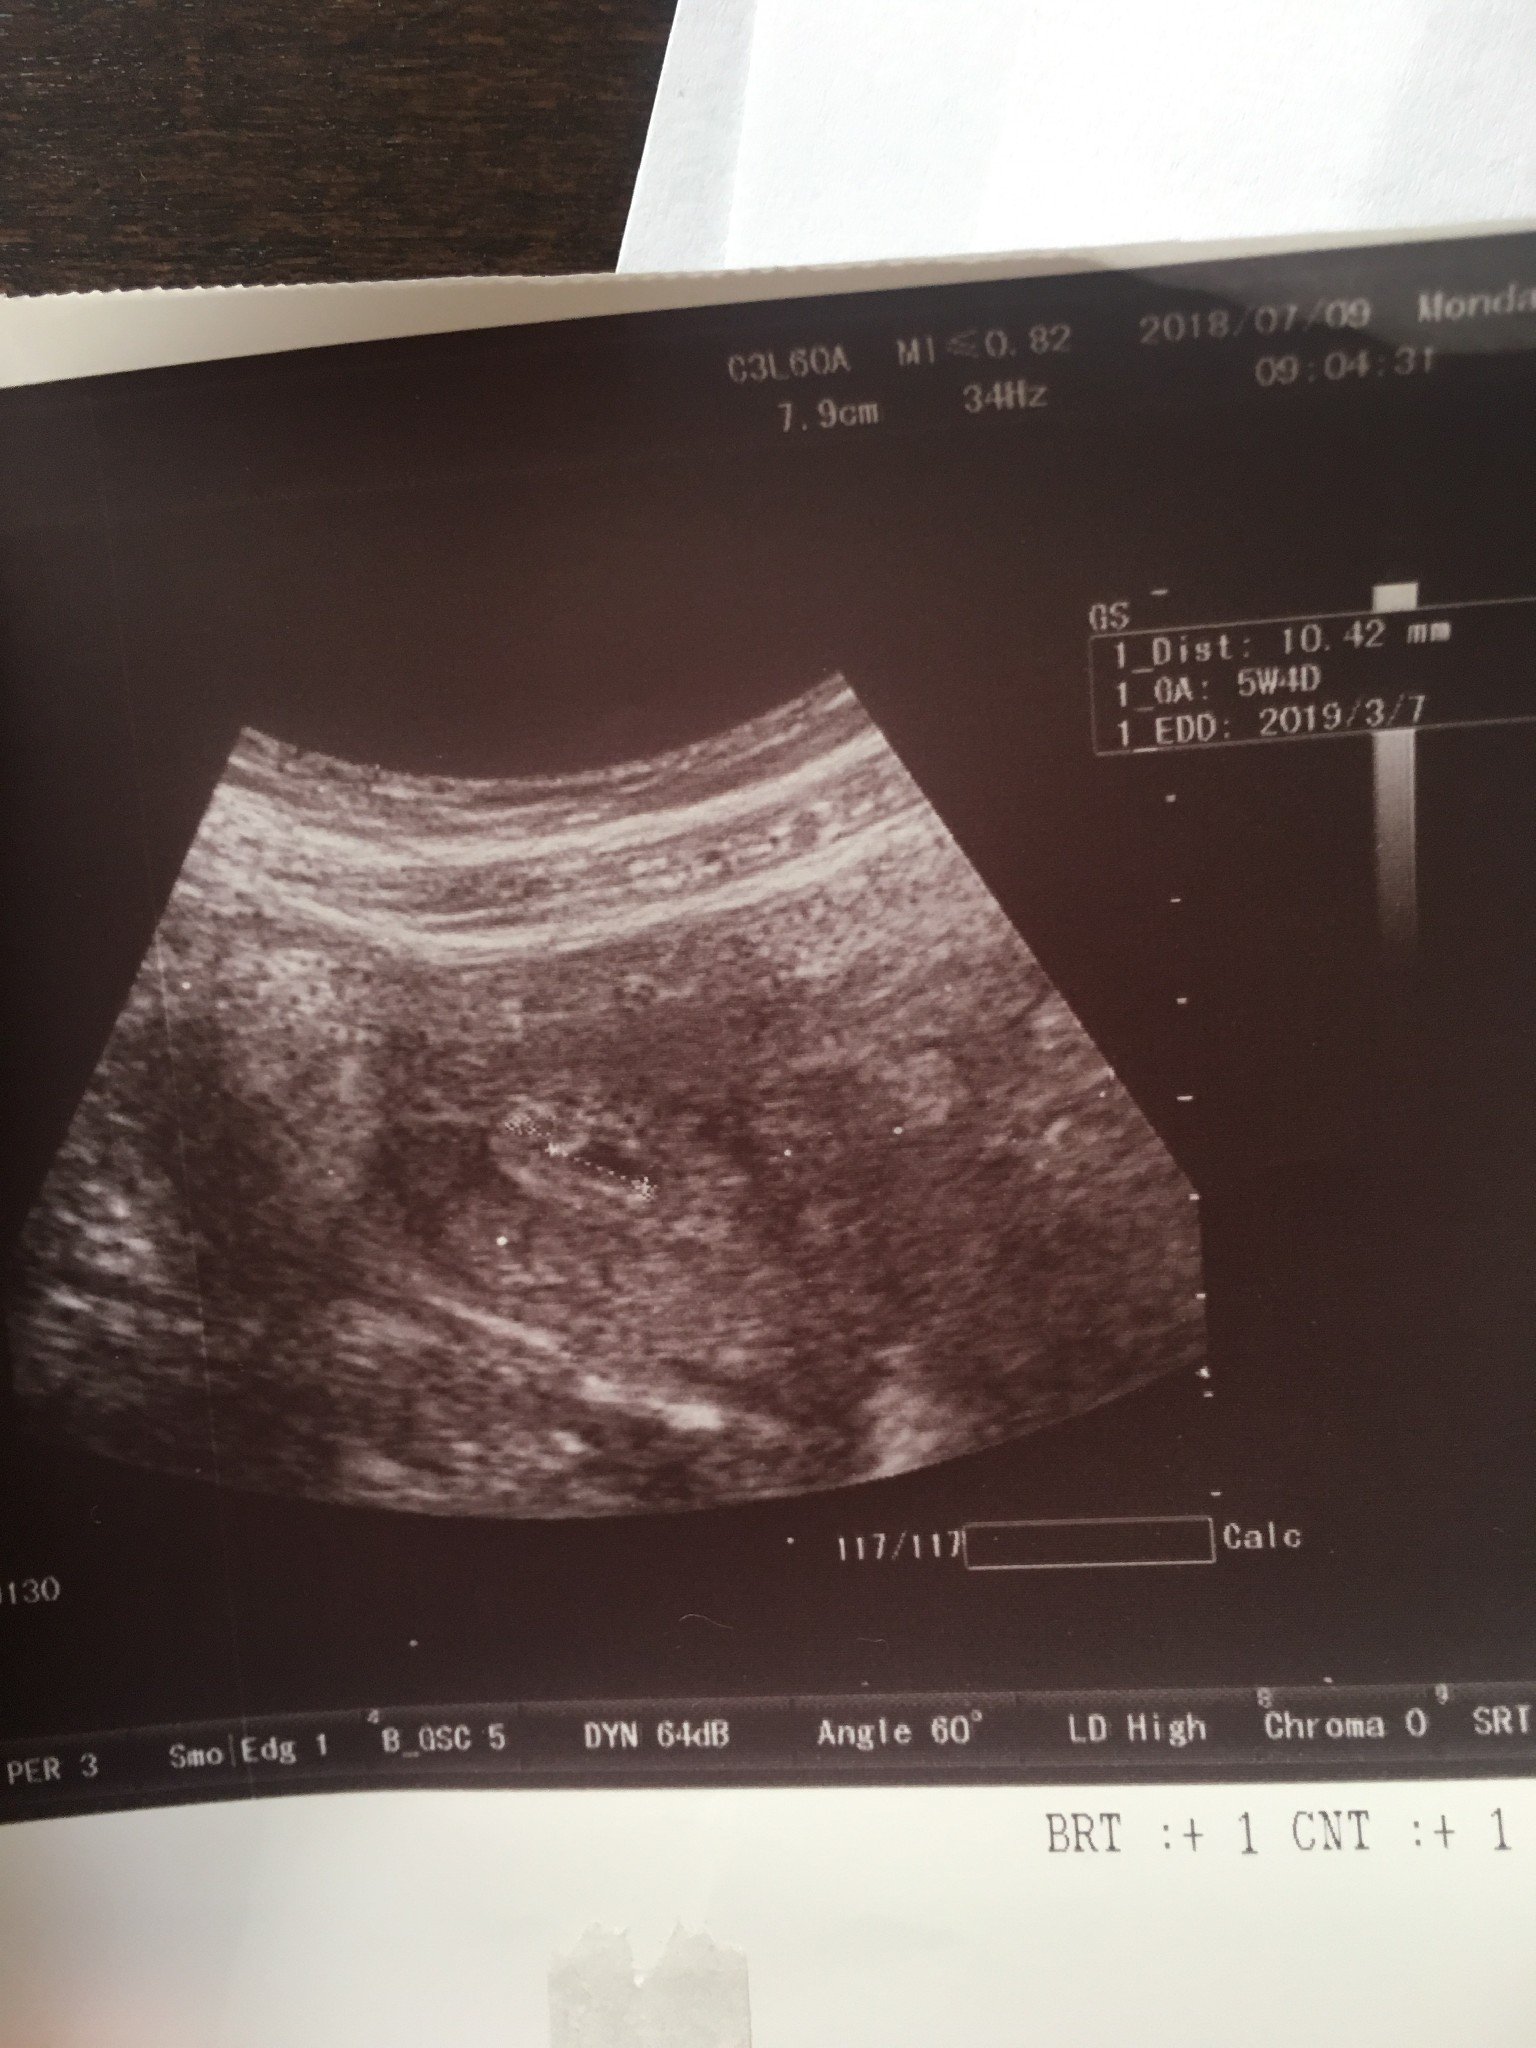

Здравейте, днес получих леко кафеникаво зацапване. Отодох на преглед, започвам дуфастона 2х1, но шпа 3х1. От последното ходене преди 6 дни, плодният сак е пораснал малко. Не знам защо се шсшкам, но смятам, че трябва да е повече. Днес трябва да съм 6с1д, а по ехограф съм 5с4д. В четвъртък пак съм на преглед.